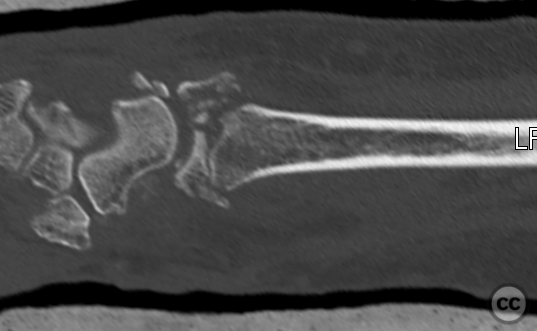

Clinical and radiological findings:  A 72-year-old female sustained a multifragmentary, dorsally displaced distal radius fracture after a fall down stairs. Initial reduction revealed a 180-degree flipped fragment of the volar ulnar articular margin, unreducible by closed means. There was no mention of associated neurovascular compromise or open injury. Radiographs and intraoperative fluoroscopy confirmed the presence of a multifragmentary intra-articular fracture (AO/OTA 23-C3), with a flipped volar ulnar fragment and radial styloid impaction. The distal radioulnar joint alignment was restored postoperatively.